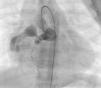

The most frequent symptoms were murmur and/or fatigue. All fistulas were congenital. Five patients (42%) had concomitant cardiac disease: pulmonary atresia with intact ventricular septum (1), patent ductus arteriosus (1), ostium secundum atrial septal defect (1), stenotic bicuspid aortic valve (1), and critical pulmonary stenosis operated in the neonatal period (1). Selective angiography was performed to delineate the anatomy of the fistula(s), which were embolized in the most distal part, sparing all the collateral branches. In one patient an arteriovenous loop was formed through the fistula, embolizing the terminal part of the fistula from the right atrium. The patients were heparinized (100UI/kg in children and 5000UI in adults) and were subsequently monitored by assessing activated coagulation time. Three patients had two fistulas, while the others had a single lesion. All fistulas were hemodynamically significant. They originated in the territory of the right coronary (10), left coronary (3) and circumflex (2), draining into the right ventricle (5), pulmonary artery (6), right atrium (2) coronary sinus (1) and left ventricle (1). Embolization materials included 15 standard coils in three patients, a Jackson® coil in one patient (Figures 1–3), 27 microcoils in 11 patients (18 standard microcoils in seven patients and nine GDC microcoils in four patients), and an Amplatzer® duct occluder in one patient (Figures 4–7). The GDC microcoils, both standard and complex, deserve particular mention, as release of these devices is controlled by electrolysis. The procedure is thus reversible up to the last stage of release, following confirmation of correct positioning. An Amplatzer® cardiac plug was tested in one patient but was not released due to its unsuitability for the lesion.